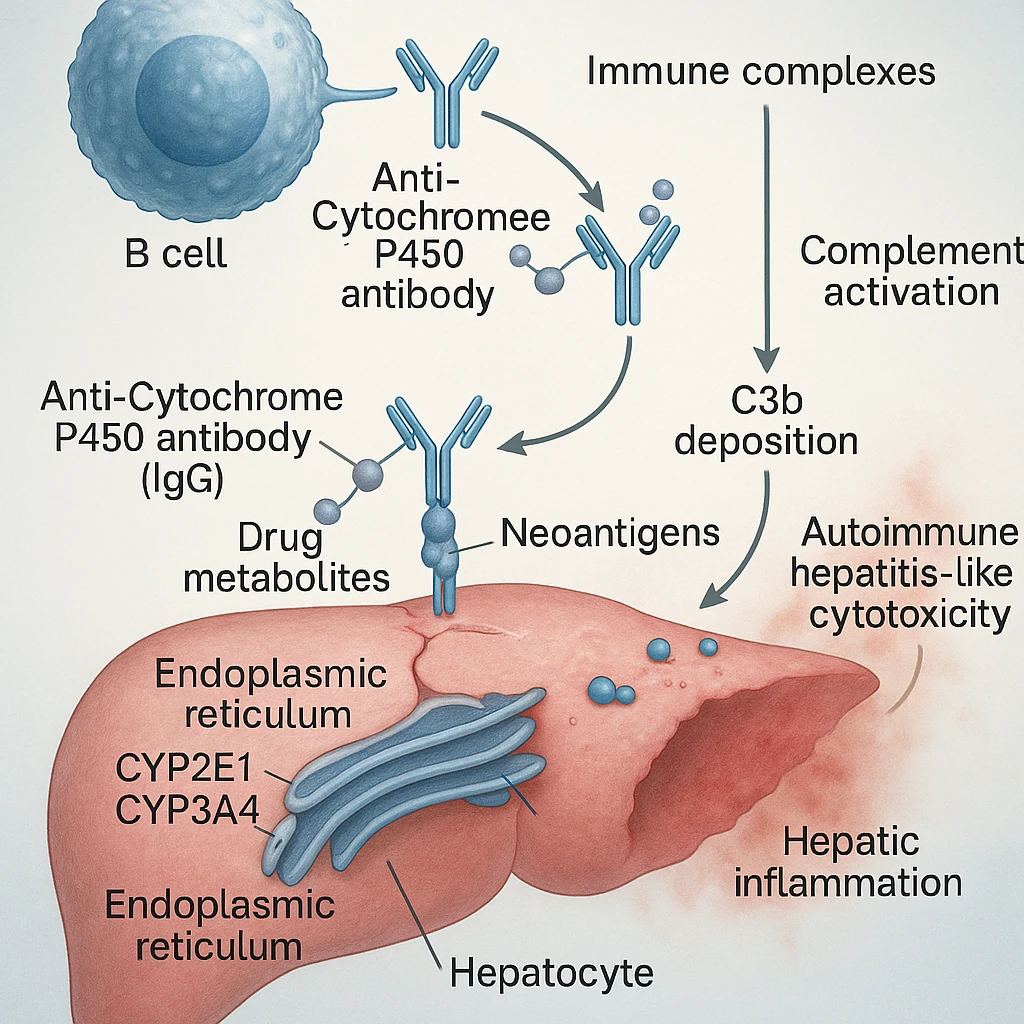

مکانیسم احتمالی:

– تغییر ساختار آنتیژنهای سلولی در اثر متابولیت دارو

– تشکیل کمپلکسهای ایمنی در بافتهای عصبی و اندوتلیال

– تحریک سلولهای T و B و تولید آنتیبادیهای ضد هیستون و ANA